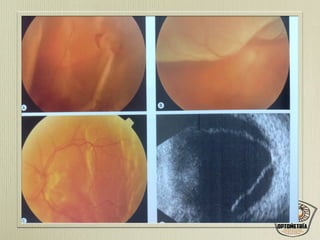

• #76 Desgarro en U en retina desprendida Desprendimiento de retina bulloso Desprendimiento de retina temporal superficial Ecografía bidimendional desprendimiento de retina total